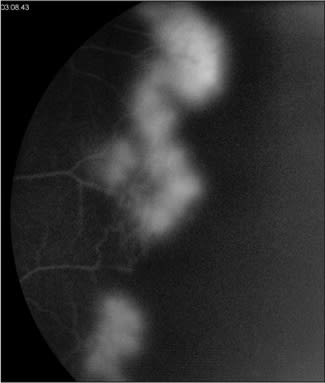

On examination, his corrected visual acuity was 20/70 in the right eye and 20/40 in the left. The anterior segment was benign with the exception of bilateral 1-2+ nuclear sclerotic cataract. The right eye had vitreous hemorrhage with a few tiny white crystals visible in the inferotemporal macula (Figure 1). Similarly, the fellow eye had white crystalline deposits scattered throughout the macula; the majority were located within the macular capillary network (Figure 2). On fluorescein angiography there was bilateral peripheral non-perfusion with adjacent late leakage of dye, which correlated with small fronds of retinal neovascularization evident on clinical examination (Figures 3 to 6).

Figure 3. Leakage from peripheral retinal neovascularization, left eye.

Figure 4. Late FA frame showing nonperfusion peripheral to the leakage, left eye.